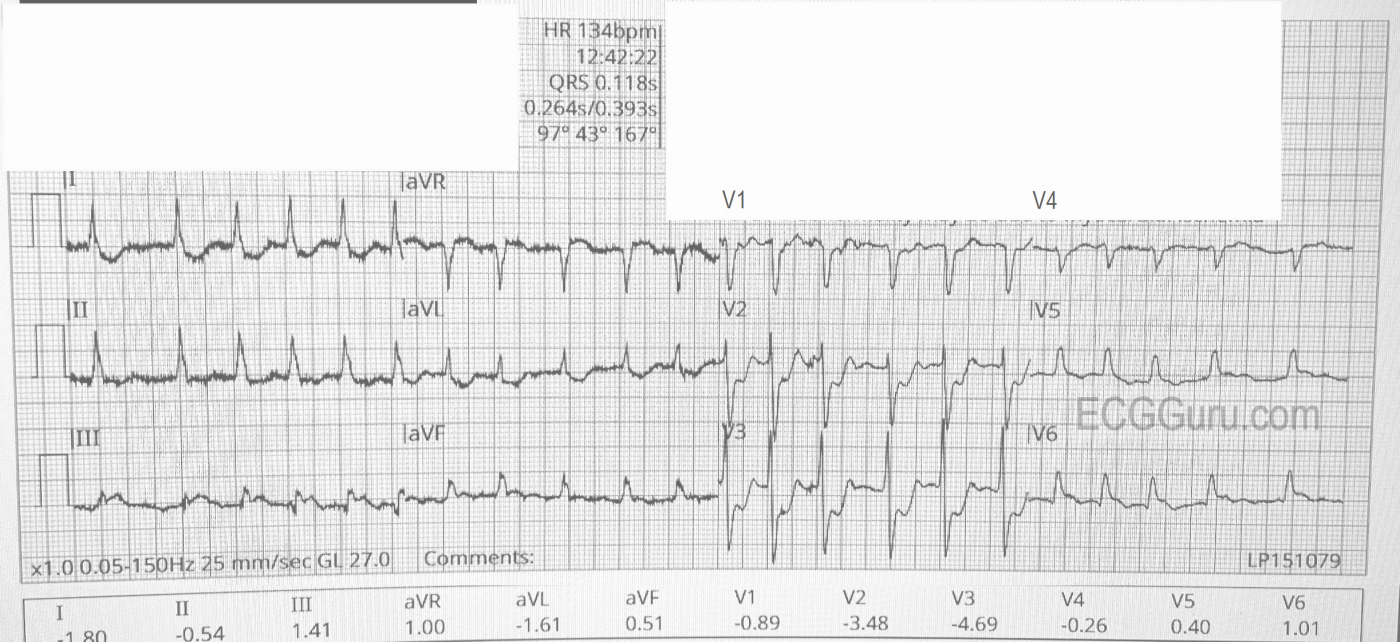

The ECG (from EMS):

The rhythm is atrial fibrillation with a rapid ventricular response (about 134/min.). The QRS width is .118 seconds (118 ms). The frontal plane axis is slightly to the left, but WNL. The R wave progression mostly normal, but V4 is incongruous. V2 and V3 have a tall R wave, possibly representing a pathological Q on the posterior side. There are ST CHANGES in every lead. ST elevation is noted in III, aVF, aVR, V5 and V6, representing ischemia in the inferior wall. There is ST depression in all other leads, indicating widespread subendocardial ischemia and/or acute reciprocal depression. Interesting that Lead II would normally be elevated when III and aVF are, but aVR is elevated, causing reciprocal ST depression in Lead II. So, Lead II looks almost normal.

The pattern of ST elevation in aVR with widespread ST depression can indicate:

1) Proximal occlusion of LCA

2) Severe triple vessel disease

3) Any condition that results in cardiogenic shock

Often, there is also STE in V1 in this situation, but V1 – V3 show signs of posterior MI, with definite ST depression and tall R waves in V2 and V3.

It is obvious that this patient’s condition is extremely dire, and he would earn a trip to the cath lab on symptoms alone in most places. An inexperienced observer might not recognize the importance of the ST elevations, since they are not large, but the pattern of elevation and the widespread ST depression is very alarming.